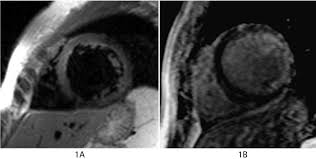

The Radiology Assistant Ischemic And Non Ischemic Cardiomyopathy

The Radiology Assistant Ischemic And Non Ischemic Cardiomyopathy from radiologyassistant.nl

More specifically, it is described as. Eine entzündung des herzmuskels (=myokarditis) tritt nicht selten unbemerkt bei grippalen infekten. Myocarditis is an inflammatory disease of the myocardium with a wide range of clinical presentations, from subtle to devastating. Mrt in der diagnose und monitoring neurodegenerativer erkrankungen. Myocarditis cardiosclerosis is a pathology in which parts of the myocardium involved in inflammation die and are replaced by connective tissue. Classified as idiopathic, these cases are attributed to genetic factors, viral myocarditis, and autoimmune mechanisms. Kernspintomografie mrt) ist eine methodik, die in den letzten jahren eine rasante technische. Journal of the american college of cardiology vol.